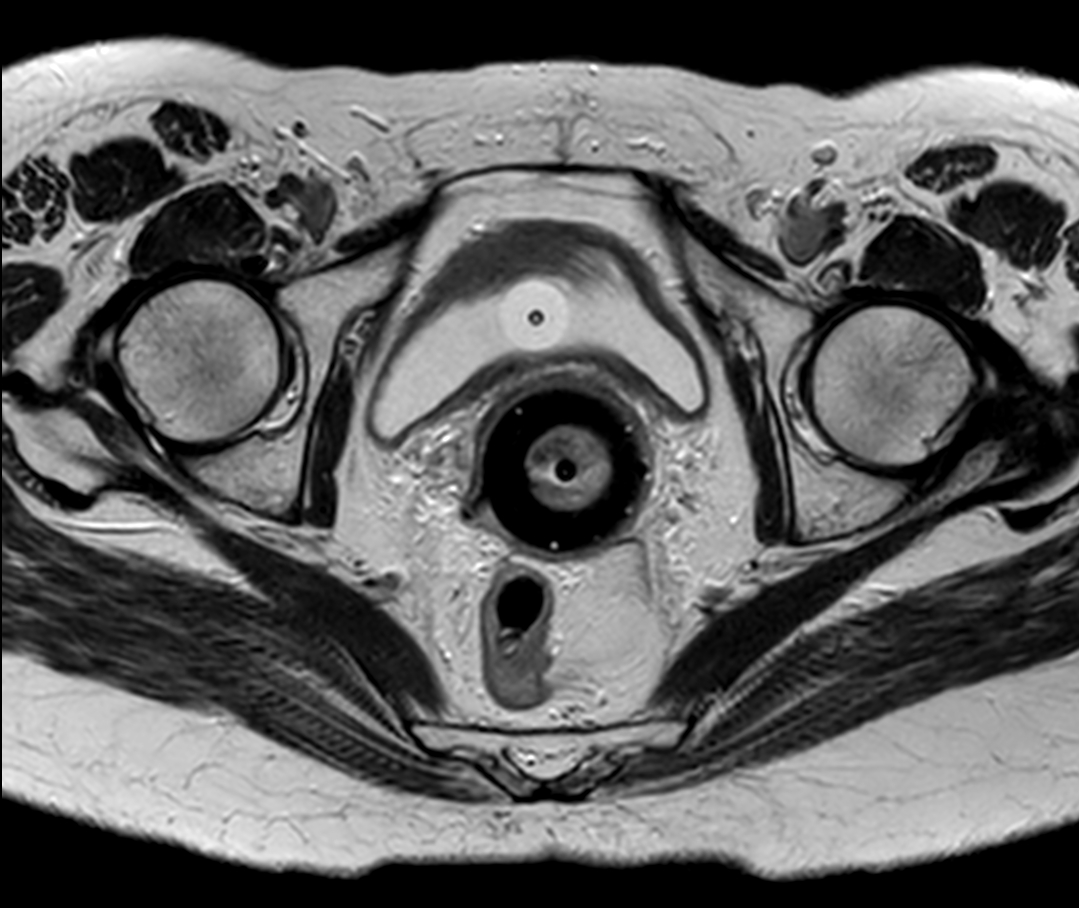

Patient with cervical cancer referred for MR-guided brachytherapy. MR imaging on Ingenia 1.5T with tandem-ring applicator in place for brachytherapy planning.

Axial oblique 2D T2w TSE